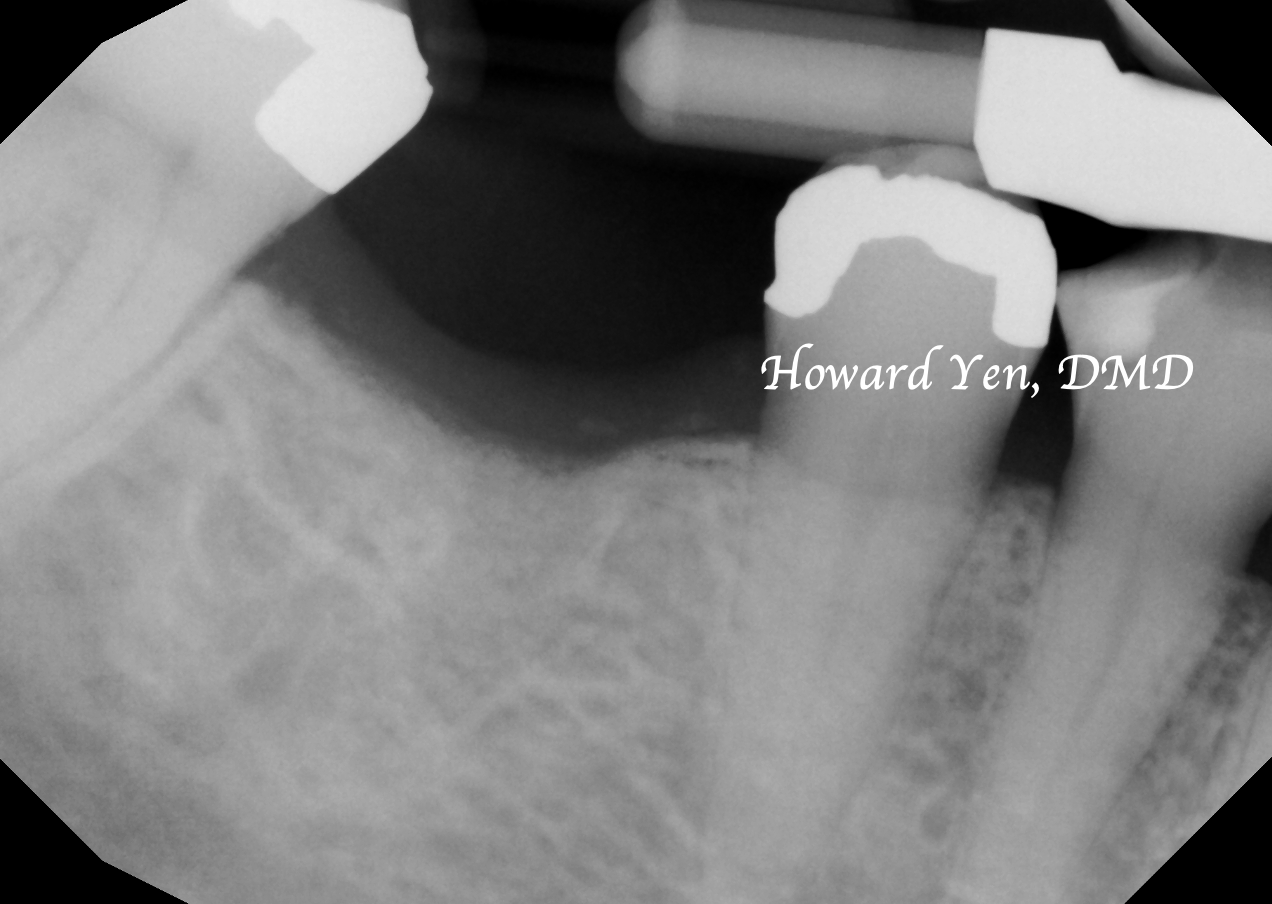

Once a natural tooth is removed from jaw bone, the jaw bone will undergo resorption (shrinkage) in volume. When there is a plan to replace the extracted tooth with dental implant, then there’s some treatment strategies to help reduce the rate of jaw bone shrinkage in order to provide adequate bone volume to receive dental implant. This procedure is often NOT necessary if there’s no plans to replace the tooth nor a strategic value (such as wisdom tooth extractions, the furthest molar in the mouth).